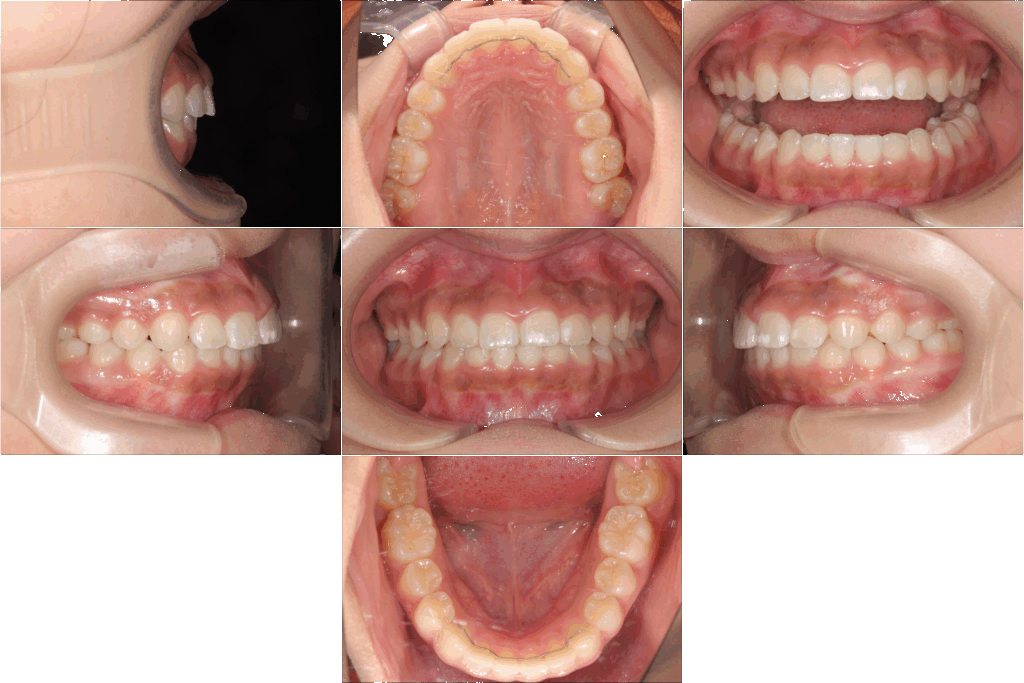

マルチブラケット装置で最終仕上げ

本格矯正のステップでは、いわゆる「マルチブラケット装置」を装着しました。

歯の表面にブラケットをつけ、ワイヤーの弾性を利用して1本1本の歯を理想的な位置へと誘導していく治療法です。

このお子さんの場合、拡大と遠心移動の段階をしっかり行っていたため、歯を抜かずにきれいな歯列を実現できました。

マルチブラケット装置の装着期間は約1年。治療初期に比べて、歯並びは見違えるほど整いました。

笑顔の印象が大きく変わり、咬み合わせの機能面も安定しました。

ブラケットを外した後はリテーナー(保定装置)を装着し、整った歯並びがしっかり安定するよう管理を続けます。